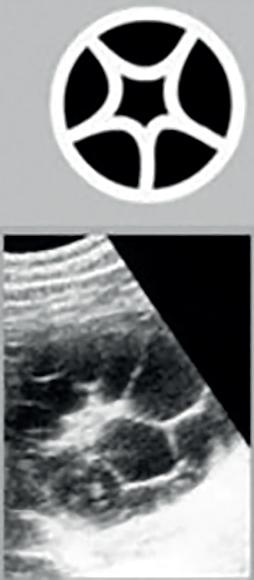

The Positive Effect of Water Immersion on Labor Progress Assessed by Intrapartum Ultrasound Examination

Pozytywny wpływ zastosowania immersji wodnej na postęp porodu oceniany metodą ultrasonografii śródporodowej